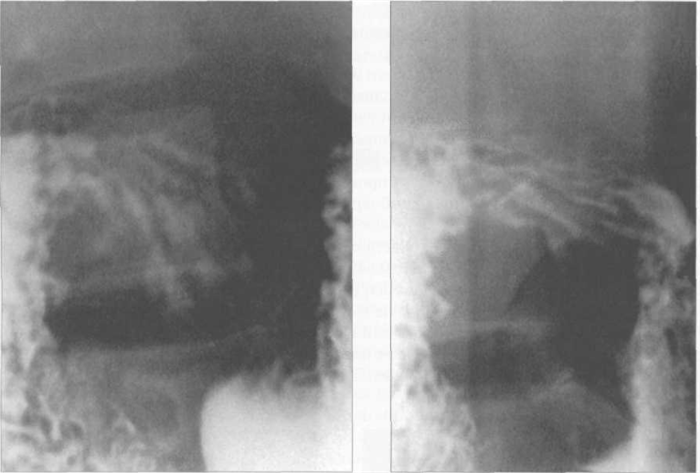

Рис. 11.36. Рентгенограммы рельефа слизистой луковицы двенадцатиперстной кишки в правом косом положении.

При рентгенологическом исследовании видны тени петель тонких кишок. Петли тощей кишки расположены частью горизонтально, частью вертикально, слева и посредине брюшной полости.

Петли подвздошной кишки находятся в области правой подвздошной ямки и имеют чаще вертикальное и косое расположение, образуя конгломерат.

Рельеф слизистой оболочки. В тощей кишке поперечные складки придают наружным контурам тени фестончатый или перистый характер, что является характерным признаком тонкой кишки; в определенные фазы перистальтики, как и в желудке, наблюдается образование продольных и косых складок. В подвздошной кишке по мере приближения к толстой число продольных складок увеличивается. Продольные складки образуют желоба и каналы для прохождения пищи, а поперечные несколько задерживают продвижение ее. Вследствие перемещения всех этих складок получаются разнообразнейшие рентгенологические картины.

Рентгеноанатомия тощей и подвздошной кишок . При заполнении контрастной массой петли тощей кишки определяются лежащими почти вертикально, а подвздошной - горизонтально, нижние петли подвздошной кишки на уровне левой боковой области живота образуют сплошной теневой конгломерат. Ясно определяется терминальный отрезок подвздошной кишки у места впадения в слепую. На рельефном снимке (при небольшом заполнении кишки контрастным веществом) видны поперечные складки, а в середине образуется полоса сплошной тени - центральный канал. Заметны различия в высоте складок.